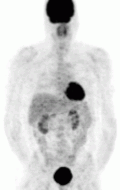

Of the four above mentioned modalities, 18F-FDG PET is the most common and readily available functional imaging technique at most hospital systems, but the least-specific to neuroendocrine tumors (Image Left). In 2012, over 200 patients participated in a trial that compared the current gold standard of the time (MIBG/CT/MRI) to the novel FDG PET. Compared to its functional counterpart, FDG outperformed MIBG in detecting soft-tissue and bone metastases with higher specificity in patients with biochemically active tumors.[80]